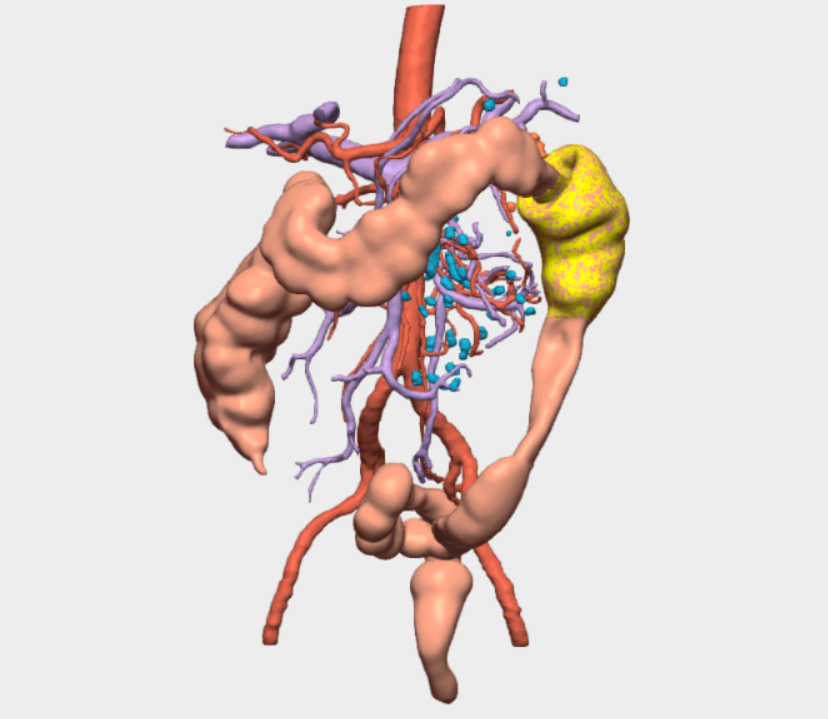

En el protocolo de prehabilitación (GRAMGEA) se detecta déficit leve de Factor VII, valorado por Hematología, indicándose vitamina K preoperatoria. El paciente pesa 80 kg, mide 177 cm (IMC 25) y es clasificado como ASA I. Se administra bolo de hierro IV (1500 mg) y se indican ejercicios de fisioterapia respiratoria. En quirófano se dispone de un modelo 3D virtual personalizado, basado en las pruebas de imagen del paciente, visible y navegable durante toda la intervención, lo que permite una cirugía dirigida, precisa y personalizada. Se localiza la tumoración en el ángulo esplénico, con gran induración, neovascularización e invaginación colocólica, hallazgos correlacionados con el modelo 3D. Se identifica la vena mesentérica 2 inferior (VMI) y se realiza disección mesocólica respetando cola de páncreas, bazo y fascia de Toldt izquierda.

Gracias a la reconstrucción 3D, se identifican dos arterias cólicas izquierdas procedentes de la Aorta, además del tronco de la cólica izquierda de la Arteria Mesenterica Inferior (AMI) permitiendo una ligadura vascular selectiva, respetando la arteria mesentérica inferior y la cólica izquierda más distal que no interesa la tumoración ni el margen de resección de seguridad, optimizando de esa manera la colectomía segmentaria del ángulo esplénico. Se realiza además sección de la rama izquierda de la cólica media.

La reconstrucción 3D fue especialmente relevante en la identificación y comprensión de la anatomía vascular mesentérica, donde se objetivó la presencia de dos arterias cólicas izquierdas, una variante anatómica con impacto directo en la estrategia quirúrgica.

Asimismo, permitió anticipar la localización exacta del tumor en el ángulo esplénico, su relación con la invaginación colocólica y con estructuras críticas como el páncreas y el bazo, reduciendo la incertidumbre intraoperatoria y aumentando la seguridad del procedimiento

El modelo 3D de CELLA permitió una visualización interactiva y navegable en tiempo real, con segmentación detallada de vasos, colon, mesocolon y órganos adyacentes. La posibilidad de rotar, aislar estructuras y correlacionar la imagen virtual con la anatomía real durante la cirugía fue clave para la identificación vascular precisa y la planificación de una resección segura. Esta funcionalidad aportó un valor diferencial al facilitar una cirugía más predecible, personalizada y eficiente, con mínima pérdida hemática y excelente evolución postoperatoria.